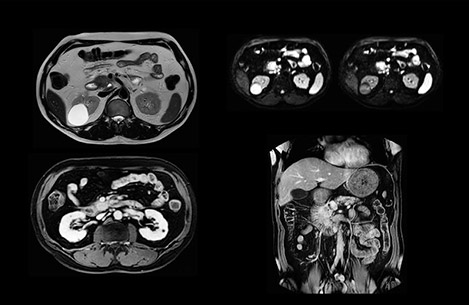

“Our liver exams are quite fast,” says Dr. Baumann. “If the patient tolerates it, we use an arms-up position to reduce the FOV and speed up the exam with dS SENSE.”

“We acquire one transversal high resolution T2-weighted sequence with 3 mm slice thickness, for example for pancreas or liver lesions. Then we also add a T2 fat suppressed MultiVane XD SPIR sequence. We perform these two routinely in our liver imaging. We use high dS SENSE factors to significantly shorten scan times to 2-4 minutes, which can improve our protocol; it’s a very robust scan.”

“We include mDIXON for the dynamic sequences because of the robust and homogeneous fat suppression we get with that. We had been using eTHRIVE, but we are now quite happy with mDIXON. Sometimes we use a medication to calm the bowels, to further improve the image quality.”

“We are more confident in our diagnosis if we don’t have to rescan the patient and compare it to other studies; this liver exam gives us good image quality in a faster time than the default system’s approach with arms down. That makes a difference for the patients, too. The shorter scan times, especially with the high dS SENSE factors, shorten the duration of the total examination. At the same time it’s more comfortable for the patient, to rest normally without holding the breath, just relaxing.”